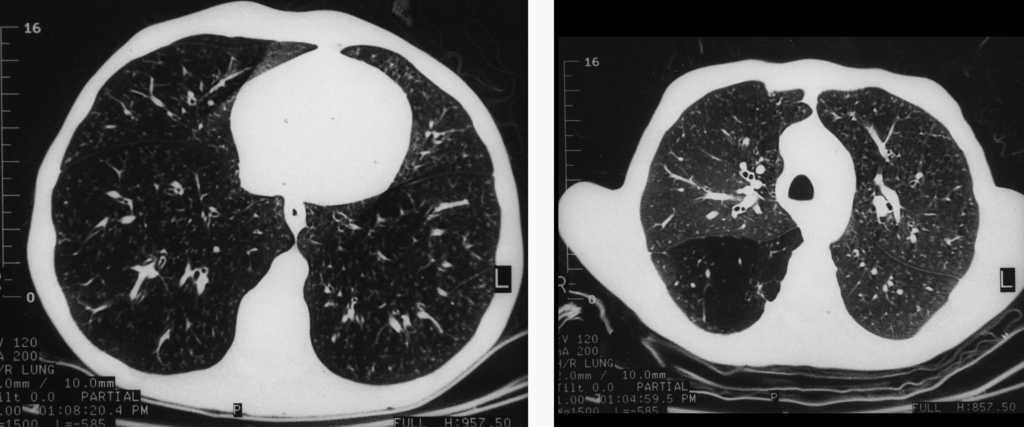

Al ingresar, la temperatura era de 36 °C, no presentaba adenopatías y en la exploración pulmonar mostraba crepitantes difusos. No se detectaron esplenomegalia, hepatomegalia ni masas abdominales. El examen neurológico, con la excepción de debilidad difusa, era normal. El recuento de leucocitos era de 2.600/μl con un 73% de células polimorfonucleares, un 10% de linfocitos y un 17% monocitos. La carga viral de 314.000 copias y la cifra de linfocitos CD4 de 80/μl. El hematocrito era del 34% y las plaquetas de 110.000/μl. Los valores de química hemática eran normales, excepto los valores de aspartatoaminotransferasa (82 U/l), gammaglutamiltranspeptidasa (193 U/l) y sodio (127 mEq/l). La gasometría arterial (fracción inspiratoria de oxígeno de 0,21) mostraba una presión arterial de oxígeno de 58,5 mmHg, pH de 7,36 y presión arterial de anhídrido carbónico de 24,4 mmHg. La radiografía de tórax era normal y la tomografía axial computarizada de alta resolución (TACAR) reveló la existencia de múltiples nódulos centrilobulares bien circunscritos, opacidades lineales en brotes de árbol (patrón tree in bud) y un área localizada de atrapamiento aéreo en el lóbulo inferior derecho en el escáner en espiración (figs. 1 y 2). El análisis de esputos fue negativo para bacilos ácido-alcohol resistentes pero se detectó Mycobacterium tuberculosis en la reacción en cadena de la polimerasa. Se inició tratamiento con isoniacida (300 mg/día), rifampicina (600 mg/día) y pirazinamida (1.500 mg/día) sin cambios clínicos ni radiológicos. La fibrobroncoscopia no mostró hallazgos significativos. El broncoaspirado y el lavado broncoalveolar fueron negativos para bacilos ácido-alcohol resistentes, así como el posterior cultivo de Löweinsten a los 60 días, pero la reacción en cadena de la polimerasa de M. tuberculosis fue positiva. En el análisis del lavado broncoalveolar se objetivó: un 33% de macrófagos alveolares, un 2% de linfocitos y un 65% de neutrófilos. La biopsia transbronquial reveló un ABA (fig. 3) e histiocitos de la submucosa bronquial que contenían amastigotes intracitoplásmicos de Leishmania (fig. 4). Se comenzó tratamiento con anfotericina liposomial pero el paciente falleció un mes después. La familia rehusó la realización de una autopsia.

Figs. 1 y 2. Tomografía axial computarizada de alta resolución, donde se observan nódulos cetrilobulares múltiples bien circunscritos y opacidades lineales en brotes de rama (patrón tree in bud), así como un área localizada de atrapamiento aéreo en el lóbulo inferior derecho en escáner en espiración.

En nuestro paciente la TACAR mostró múltiples nódulos bien delimitados, de distribución difusa, presumiblemente debidos al ABA, y hallazgos indicativos de bronquiolitis obliterante, con áreas de atrapamiento aéreo e imágenes del patrón tree in bud, probablemente secundario al virus de la inmunodeficiencia humana, dado que no había otro agente etiológico asociado. Además de los estudios radiológicos, el diagnóstico de bronquiolitis se hizo a través de los resultados del lavado broncoalveolar, en el que el porcentaje de neutrófilos era superior al 50% (nuestro paciente tenía un 65%), y de la progresión de los síntomas respiratorios6. Sin embargo, no había evidencia histológica de bronquiolitis obliterante en la muestra de la biopsia transbronquial realizada, quizá debido a la exigua muestra obtenida, por lo que el diagnóstico definitivo de bonquiolitis obliterante debe considerarse con cautela, aunque el contexto clínico, radiológico y del lavado broncoalveolar eran muy indicativos, sin que la enfermedad previa pudiera explicar estos hallazgos7.